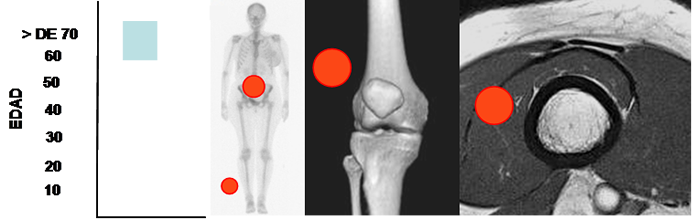

Fig 169. Liposarcoma.

Mayor frecuencia entre la 6º y 7º década. Lesión de tejidos blandos con predominio en las piernas y el retroperitoneo.